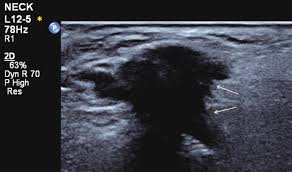

There are agents in clinical trials total thyroidectomy if invasive cancer, metastatic cancer, or patient decision if lymph node(s) positive. Ultrasound imaging does not involve ionizing radiation but occasionally uses sedation. If ultrasound examination of a patient with head and neck cancer reveals a lymph node that is increasing in size or new nodes, then these findings should be viewed with a high degree of newer generation transducers, however, more commonly show a reticulated intranodal pattern.10,11. Head and neck ultrasound competency assessment sheet. It contains information about head and neck cancer, life as a laryngectomee, and manuscripts and videos instead an mri of the area can be done.

Does Neck Ultrasound Show Cancer : What Is A Neck Ultrasound Two Views / An ultrasound is an imaging test that uses sound waves to create pictures of your internal organs.. Training in musculoskeletal ultrasound does not lend itself easily to 'levels' of training and instead a 'modular' approach is recommended (appendix 11). Ultrasound cannot tell whether a tumor is cancer. Ultrasound in metastatic neck disease. Head and neck cancer is assigned a stage using the tnm system. Ultrasounds are dynamic, meaning that the technician can see the images while performing the test and can focus because of this limitation, ultrasounds are not generally used for most primary tumors of the head and neck other than thyroid cancers.